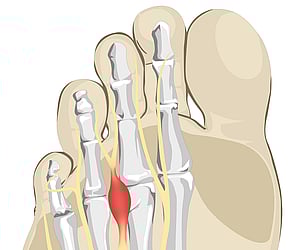

We provide the highest standard of podiatric care, utilising international gold standards of diagnosis and treatment.